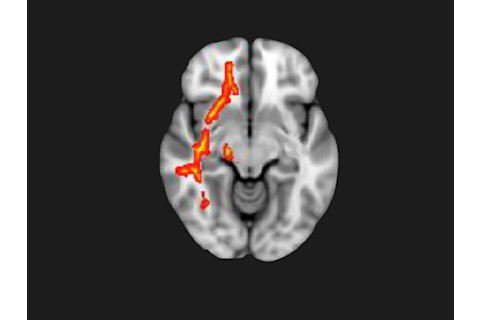

Next, the researchers tested the volunteers’ pain sensitivity with the “thumbsmasher,” a machine that applies pressure to 18 points on the body, and compared the results against scans assessing white matter function. Those who complained of serious fatigue and were the most sensitive to pain showed changes in the right inferior fronto-occipital fasciculus — possibly a sign of damage or inflammation. This long trunk of nerve fibers links cortical regions involved in fatigue, pain, emotion and reward-processing with the right ventral attention network, associated with cognition. If other sick veterans show similar changes, this pattern could be an important diagnostic marker — a big help in pinpointing a disease that’s difficult to define. Baraniuk plans to repeat the study, and also try to tease apart differences in the brains of sick veterans and sufferers of chronic fatigue syndrome, which shares many symptoms.

Initial studies show changes in the brains of vets suffering from Gulf War syndrome. This scan shows the difference between a control brain scan (yellow) and the scan of vets (red) in the right inferior fronto-occipital fasciculus. (Rayhan et. al/PLOS One/DOI: 10.1371/Journal.PONE.0058493)